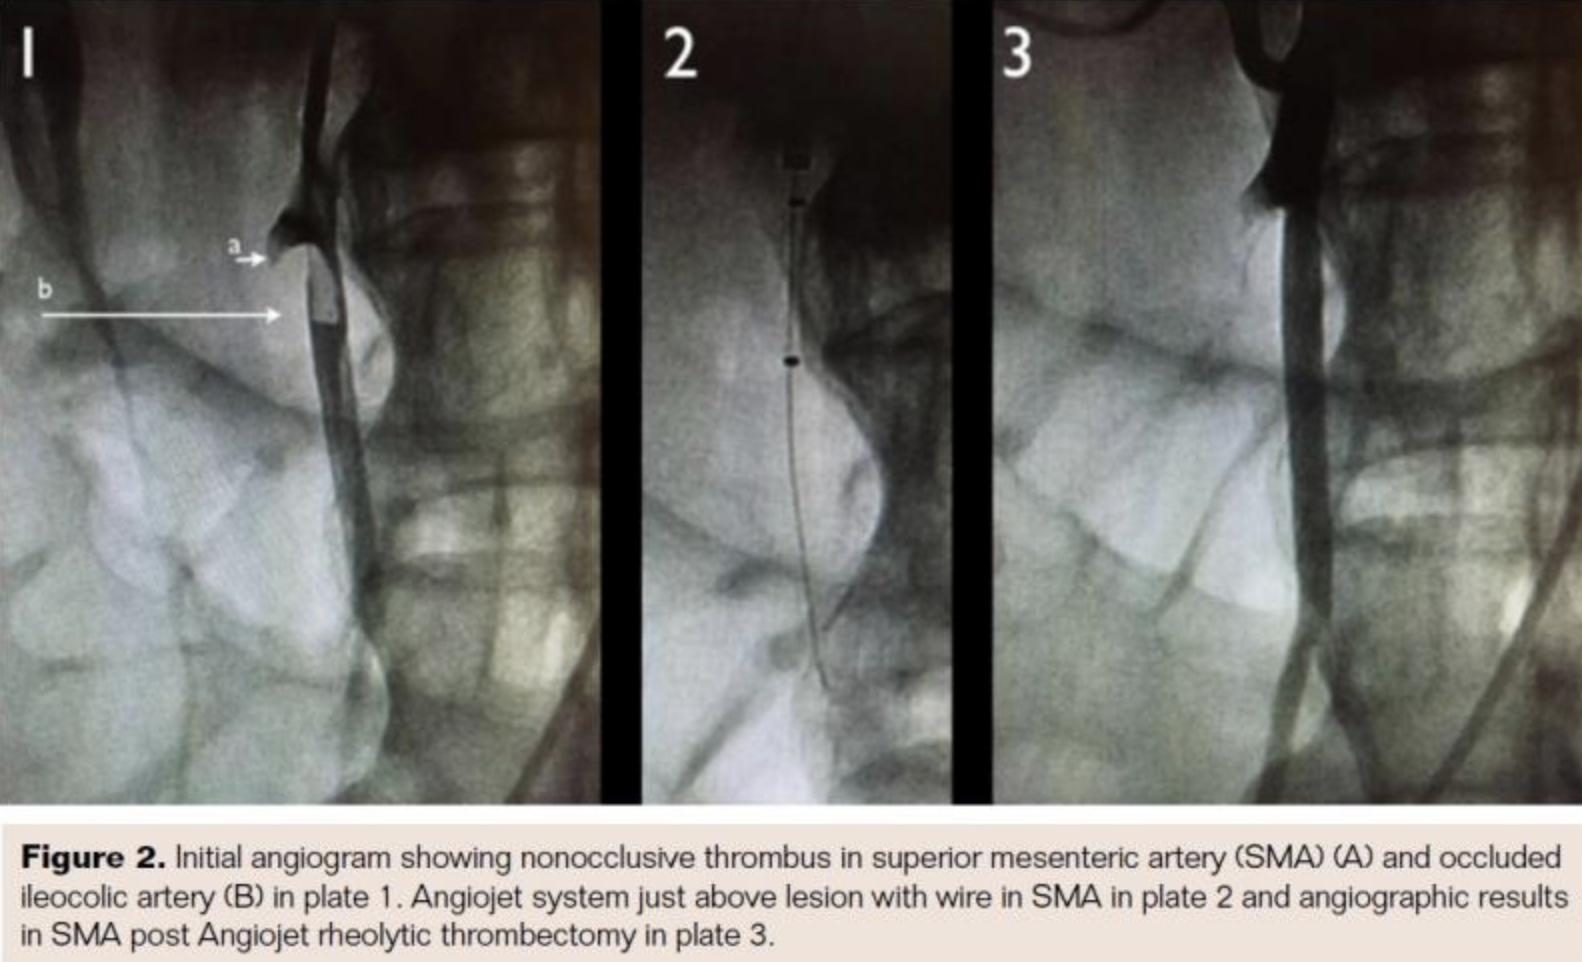

The patient was taken for urgent angiography due to rapid rise in biomarkers reflecting early bowel necrosis. Right femoral artery access was obtained and cannulated with a 6 Fr sheath. A 4 Fr internal mammary catheter was used to cannulate the superior mesenteric artery (SMA). The catheter was advanced into the proximal segment of the vessel over a Glidewire (Terumo). Angiography via the internal mammary catheter confirmed the CT angiographic findings. This catheter was exchanged for a 6 Fr, 55 cm Ansel guiding sheath (Cook Medical). Activated clotting time was 177 seconds, and heparin 3,000 U bolus was administered intravenously. A 0.014˝ wire was advanced through the occluded distal SMA and thrombectomy was done using an Angiojet XVG thrombectomy catheter with complete resolution of the thrombus (Figure 2). The wire was then advanced into the ileocolic artery, which was treated with a similar technique (Figure 3). The proximal segment of the ileocolic artery showed thrombus resolution but a large branch of this vessel was still occluded. Thrombectomy in this branch did not re-establish flow in the vessel, and the angiographic appearance was consistent with diffuse spasm. A 135 cm Cragg-Mcnamara Valved Infusion Catheter (Medtronic) with 10 cm infusion length was then advanced into this branch (Figure 4) and intra-arterial papaverine was administered via this catheter at 30 mg/hr. An intravenous heparin drip was administered peripherally at 500 U/hr.

Retrospective studies have also shown improved outcomes with routine angiography.21 Angiography has the advantage of being able to diagnose the etiology of occlusion. A large branch of the ileocolic artery was persistently occluded despite thrombectomy. Based on the angiography, this was felt to be secondary to severe spasm rather than residual thrombus. Therefore, we decided to forgo further attempts at thrombectomy or thrombolytic therapy and instead used intra-arterial papaverine along with intravenous heparin.